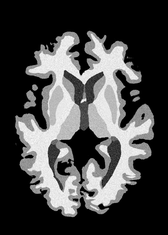

4.2 Registration to a 100 micron ex-vivo brain MRI volume

To showcase the efficacy of our method on real large scale images, we register a 250 in-vivo MRI image (Lüsebrink et al., 2017) to a 100 ex-vivo FLASH human brain volume (Edlow et al., 2019). This represents an inverse problem with more than 11.2B optimizable parameters (compared to 20M for clinical datasets), or 44.8GB of GPU memory. The entire problem does not fit on most GPUs, necessitating distributed multimodal registration. We optimize a composite transform - affine followed by a diffeomorphic mapping; details can be found in Section E.1. Multimodal deformable registration took 58 seconds on 8 NVIDIA A6000 GPUs, which is unprecedented at this resolution. Fig. 6 shows qualitative results, highlighting the ability to register highly detailed structures such as cerebellar white matter; these structures are not visible at macroscopic scales. The resultant advantages of performing registration at this scale can allow researchers to characterize the neuroanatomy at microscopic resolutions and allow morphometric analysis of cortical layers and subcortical nuclei among other structures.